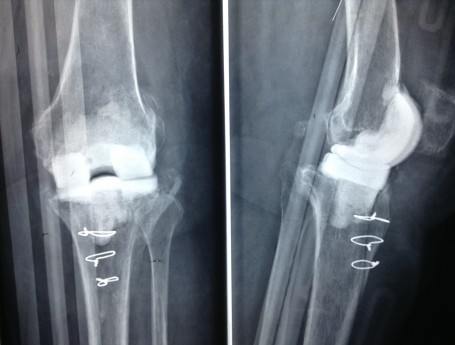

Revision Total Knee Replacement After Infection

• Revision Total Knee Replacement After Infection